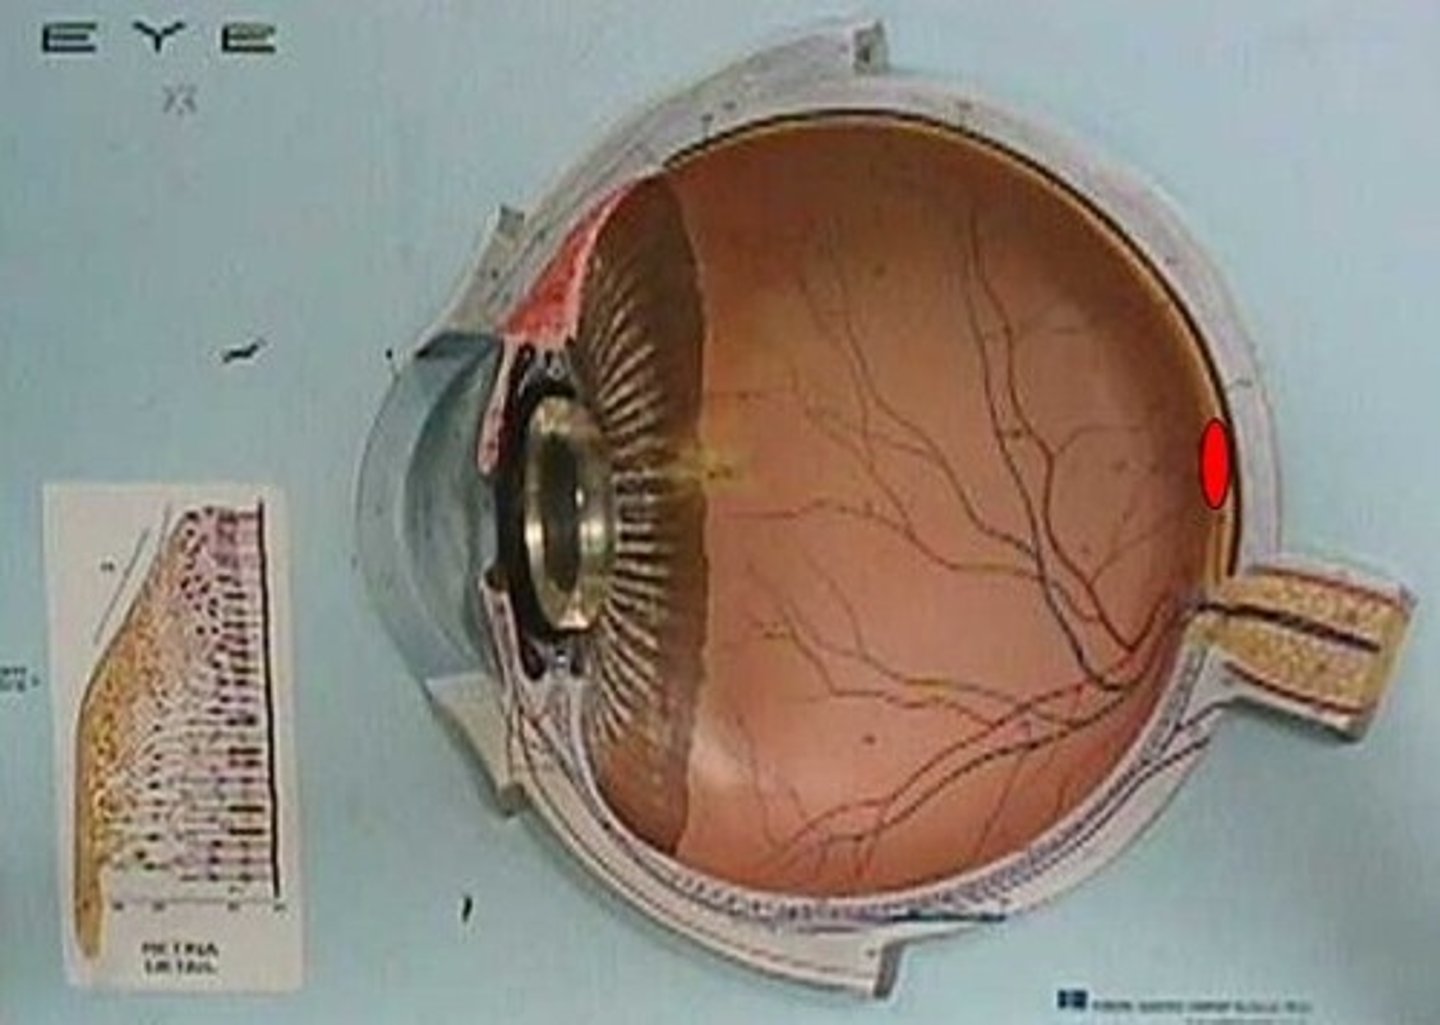

anterior cavity (of eye)

optic disk (blind spot)

choroid

ciliary body

cornea

fovea centralis

suspensory ligaments

vitreous humor

lens

macula lutea

posterior cavity (of eye)

retina

sclera

optic nerve